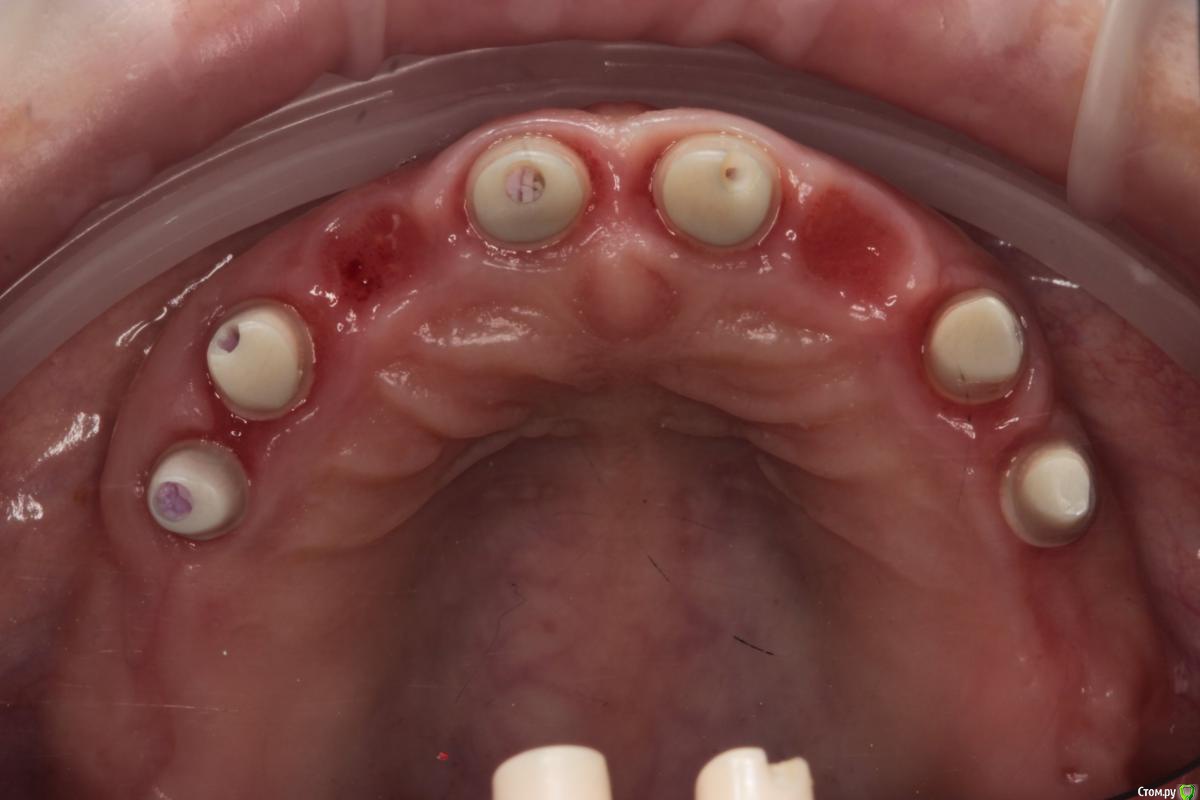

Популярный пост Abuk Опубликовано 24 ноября, 2015 Популярный пост Поделиться Опубликовано 24 ноября, 2015 Планировали 8 имплантатов.Буду рад конструктивной критике.Фото с мокап.Через 6 днейДалее хотели поставить 6 ки, она отказалась (не хотели синусы)и решили все по-другому .Через 2мес пришла с отколотыми консолями )Прошу прощения ,что ортопедию выложил не в том разделе), не хотел делить. 26 1 Ссылка на комментарий

Abuk Опубликовано 24 ноября, 2015 Автор Поделиться Опубликовано 24 ноября, 2015 (изменено) Радикально Вы. Что оставили ей после имплантации-это инд аббатменты? На них мокап одели и нагрузили сразу? У всех был торк хороший? Или это временные абб? Что за систему использовали? В планах консоль назад, правильно я понимаю?Спасибо.увидев такую работу,сам так же подумал бы). Но там подвижность 2-3 ст. ближе к 3. Мосты болтались ,2 ки в хлам. 1 ки только стабильны. Снимал мосты,проводил кюретаж. Решил дернуть.Абатманы временные, тех. сделал на них коронки. Система анкилоз. Работа,на посл. фото, постоянная . Имплы в области 4 и по одному моляру ,консоли. Мок ап был до имплантации . По нему шаблон. Стабильность 15 -20 на 23 , остальное больше 30. Изменено 24 ноября, 2015 пользователем Abuk 1 Ссылка на комментарий